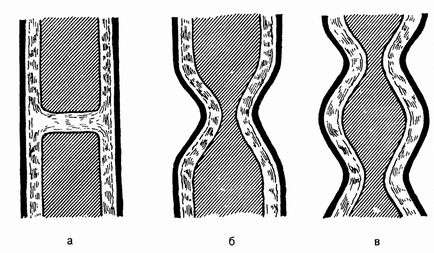

Кільця Шацького стали розділятися на 4 ступеня звуження. Основа класифікації полягає в тому, наскільки складно і довго їжа проходить через сполучна отвір між шлунком і верхнім відділом травної системи.

перша ступінь

Періодично з'являються проблеми при ковтанні їжі, больові симптоми в шлунку чи стравоході виникають рідко.

друга ступінь

У шлунок може проходити тільки напіврідка їжа (наприклад, пюре, кефір, йогурт).

третя ступінь

Без проблем через кільце Шацького може проходити тільки рідина.

четверта стадія

Дуже небезпечне протягом патології, при якій в шлунково-кишковий тракт не може потрапляти навіть вода.